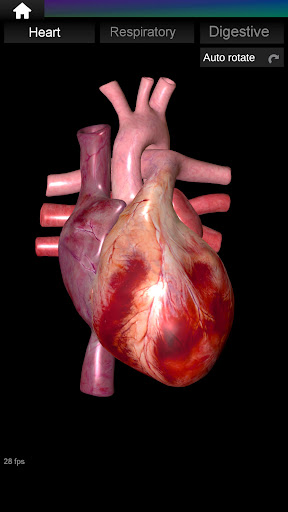

* Серце, що включає передсердя, шлуночки, аорту і одушевлення цього органу.